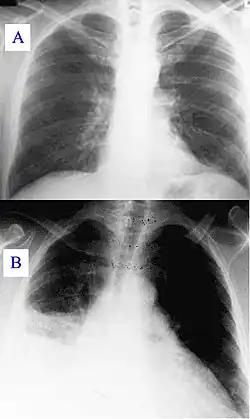

Основными методами диагностики являются рентгенологическое исследование лёгких и исследование мокроты, основным методом лечения — антибактериальная терапия. Поздняя диагностика и задержка с началом антибактериальной терапии ухудшают прогноз заболевания. В некоторых случаях возможен смертельный исход.

Диагностические методы исследования

- Рентгенография грудной клетки

- Компьютерная томография грудной клетки